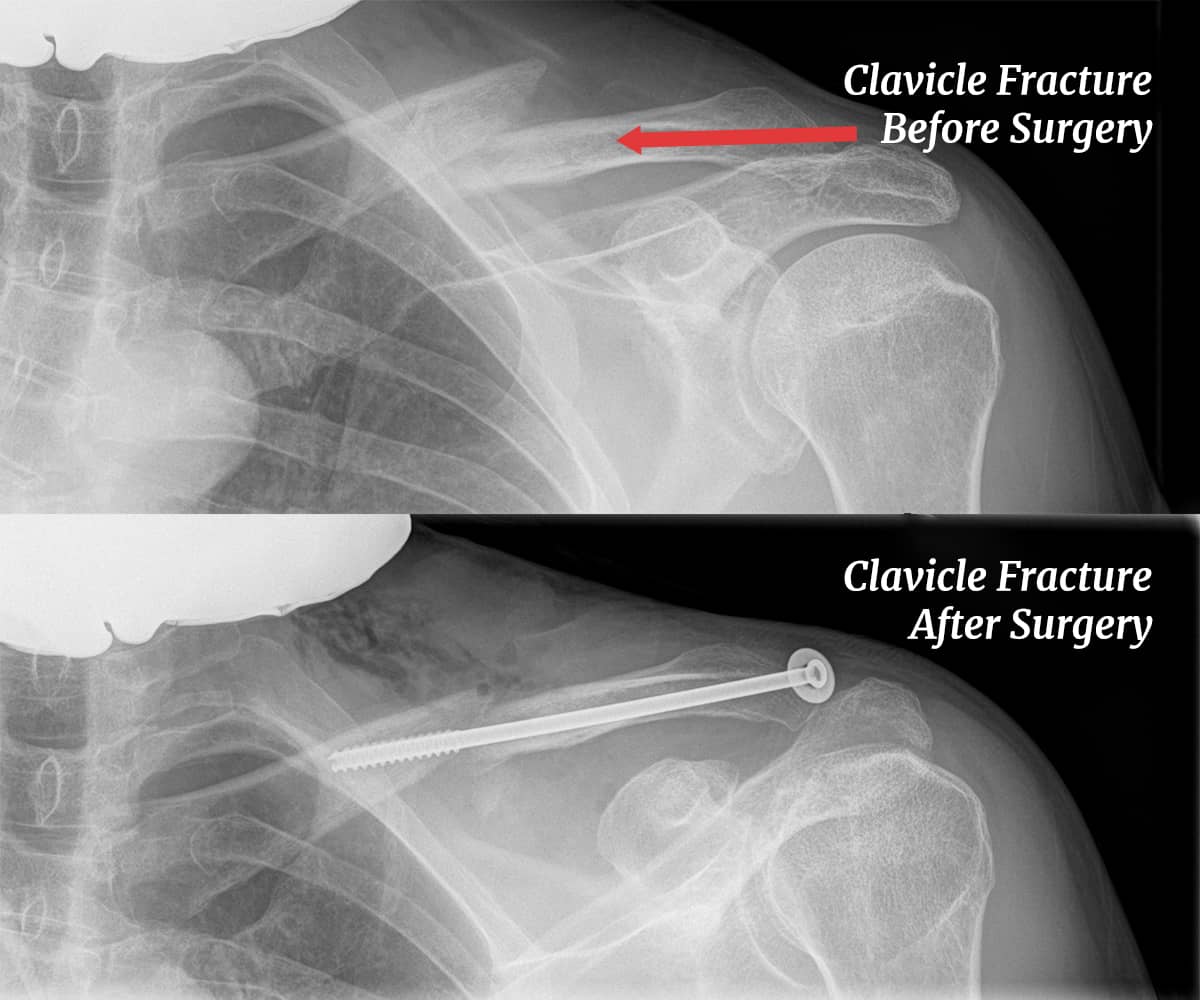

The techniques for midshaft clavicle repair are plate fixation with screws in most cases and intramedullary screw placement in a few. We are in the intramedullary camp, and here is why: Plate fixation requires a horizontal incision, which is not cosmetically pleasing and risks damaging a sensory nerve that, when cut, leaves a numb patch on the chest. The plates are prominent and often require a second surgery for removal.

Intramedullary pin fixation is done through a small vertical incision, lines up the clavicle with end-to-end compression, and is easy to remove through a small posterior incision. But since the clavicle is a twisted bone with a small central cavity, this procedure has unique risks. Additional fractures at the time of fixation and nonunion can occur.